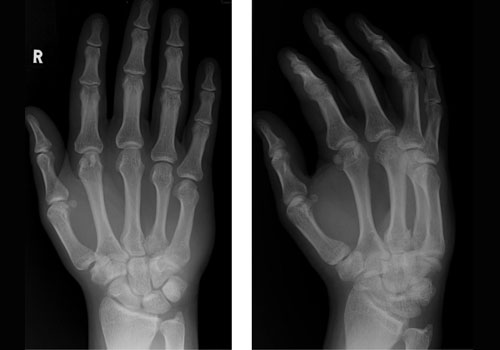

شکستگی ها

Fractures

عکس های مرتبط

photoes